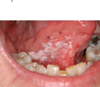

Epidemiologic and preclinical data support the oral cancer prevention potential of green tea extract (GTE). We randomly assigned patients with high-risk oral premalignant lesions (OPL) to receive GTE at 500, 750, or 1,000 mg/m(2) or placebo thrice daily for 12 weeks, evaluating biomarkers in baseline and 12-week biopsies. The OPL clinical response rate was higher in all GTE arms (n = 28; 50%) versus placebo (n = 11; 18.2%; P = 0.09) but did not reach statistical significance. However, the two higher-dose GTE arms [58.8% (750 and 1,000 mg/m(2)), 36.4% (500 mg/m(2)), and 18.2% (placebo); P = 0.03] had higher responses, suggesting a dose-response effect. GTE treatment also improved histology (21.4% versus 9.1%; P = 0.65), although not statistically significant. GTE was well tolerated, although higher doses increased insomnia/nervousness but produced no grade 4 toxicity. Higher mean baseline stromal vascular endothelial growth factor (VEGF) correlated with a clinical (P = 0.04) but not histologic response. Baseline scores of other biomarkers (epithelial VEGF, p53, Ki-67, cyclin D1, and p16 promoter methylation) were not associated with a response or survival. Baseline p16 promoter methylation (n = 5) was associated with a shorter cancer-free survival. Stromal VEGF and cyclin D1 expression were downregulated in clinically responsive GTE patients and upregulated in nonresponsive patients at 12 weeks (versus at baseline). An extended (median, 27.5 months) follow-up showed a median time to oral cancer of 46.4 months. GTE may suppress OPLs, in part through reducing angiogenic stimulus (stromal VEGF). Higher doses of GTE may improve short-term (12-week) OPL outcome. The present results support longer-term clinical testing of GTE for oral cancer prevention.